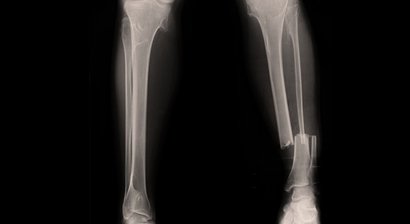

Unterschenkel Marknagel

Der Unterschenkel besteht aus dem Schien- und Wadenbein (Tibia und Fibula). Kommt es zu einem Unterschenkelbruch, sind meist beide Knochen gebrochen. Natürlich kann die Fraktur auch nur einen der beiden Röhrenknochen betreffen. Als Marknagelung oder Marknagelosteosynthese wird das Operatio...